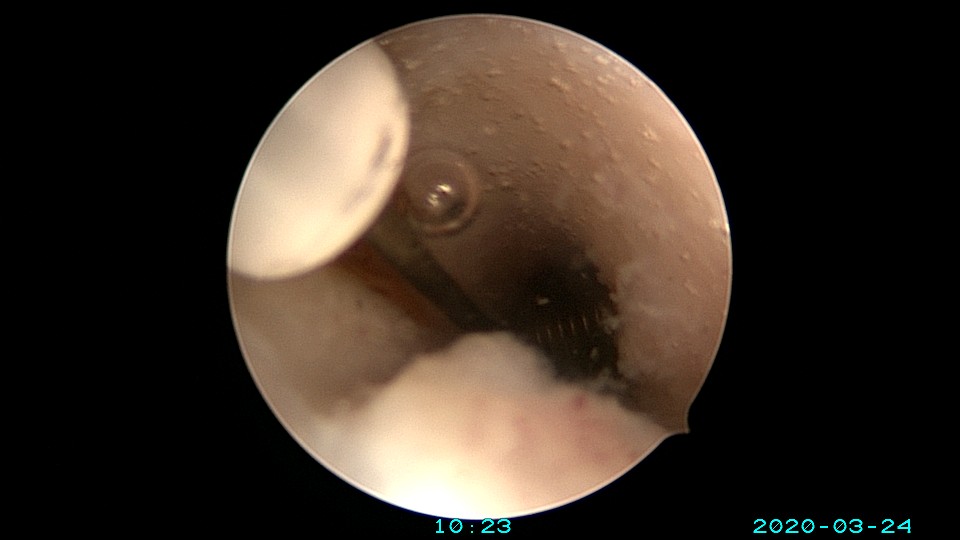

患者65岁,G1P1,顺产1次。安环30年,绝经10年。外阴白斑,阴道明显萎缩,无法置入扩阴器,阴道内镜方式找到宫颈外口,宫颈萎缩,穹隆几乎消失,无法夹持宫颈,宫颈管见多个息肉,宫颈内口狭窄坚硬,难以扩张。微型异物钳探查宫腔方向,用异物钳、微型剪刀扩大宫颈内口失败,改用双极电针切开宫颈内口,但镜子仍无法进入宫腔。用异物钳反复牵拉O型环至阴道内,中弯钳配合卵圆钳拉出节育环,环变形。有人问我何不用取环钩取环,这个病人探针和取环钩都无法发挥作用。